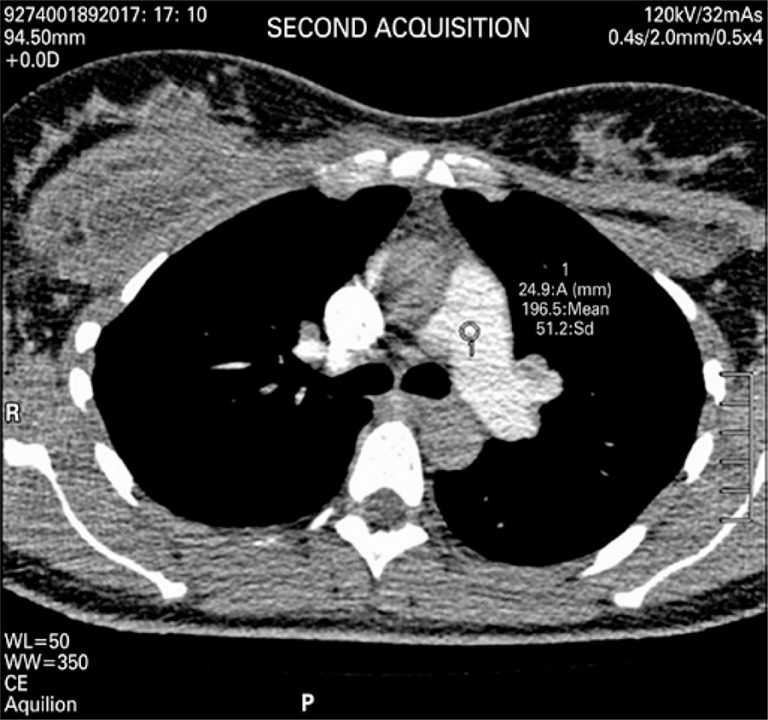

This was 37-year-old woman, 10 days after surgery, who underwent breast prosthesis replacement, abdominoplasty and liposuction. Upon admission, she was hemodynamically stable, febrile and reported constant pain on left hemithorax region, but without dyspnea.

An angio-CT of thoracic vessels was carried out. During intravenous injection of contrast agent, the patient was anxious and started crying during the exam. We believe that, a Valsalva maneuver was performed on inspiration apnea requested during the exam therefore causing an intrathoracic pressure that resulted only in a thoracic aortic contrast (). A new contrast agent was intravenously injected after apnea orientation, and the Valsalva maneuver was not requested, which resulted in precisely diagnostic images (). Two acquisitions were carried out using manual trigger when peak of pulmonary artery contrast occurred ( and ).